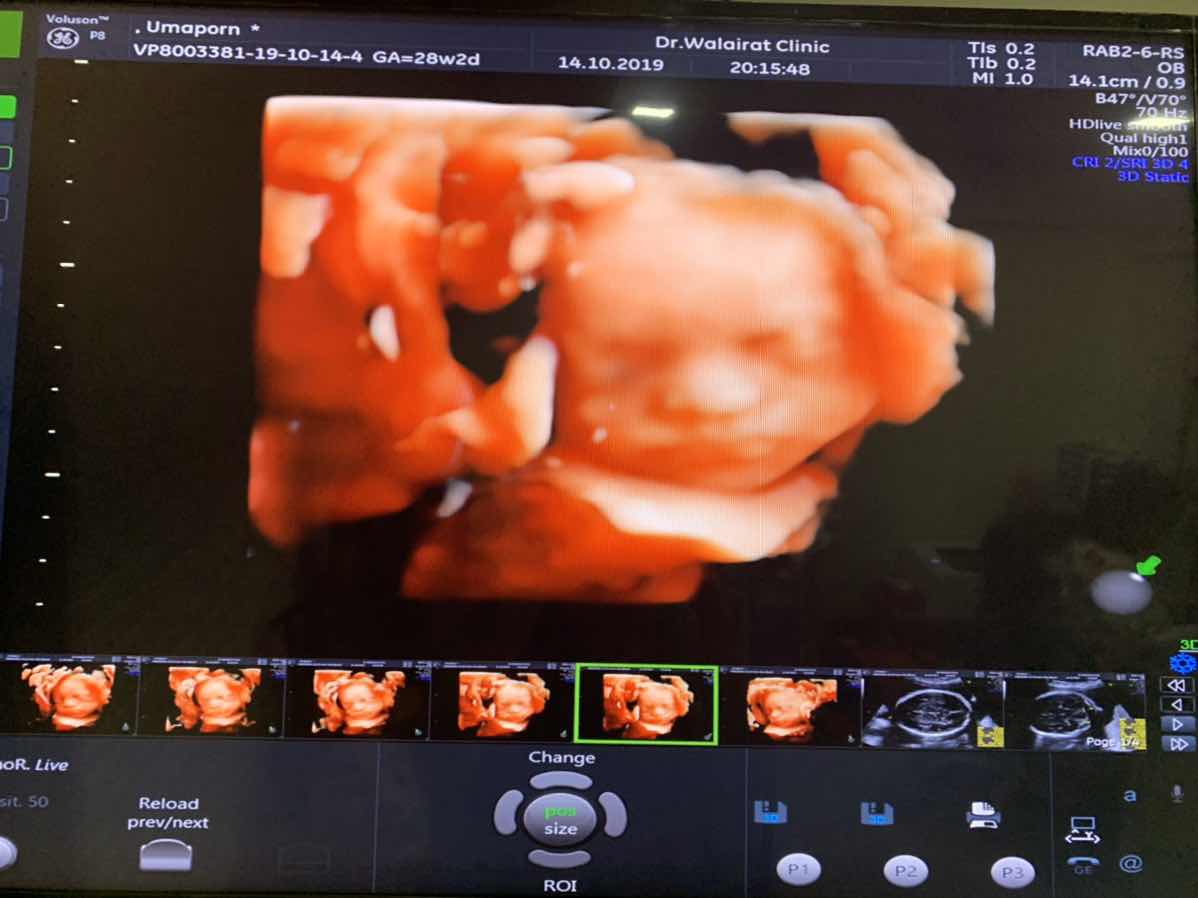

บ้านนี้ซาวตอน 28W จ้า